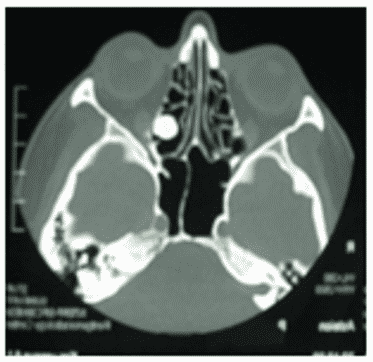

Остеобластома на КТ обычно представлена сочетанием плотной кости и участков затемнения (рисунок 4).

Рис. 4. КТ черепа, аксиальная плоскость. Гигантская остеобластома, распространяющаяся в правую орбиту, полость носа и переднюю черепную ямку

Данные КТ позволяют определить признаки локально агрессивного роста остебластомы, место ее исходного роста, наличие/отсутствие распространения опухоли за пределы околоносовых пазух.